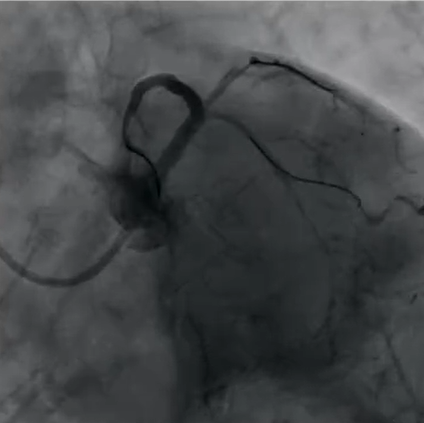

(Case 1术后)

Case 2:前降支对角支分叉处病变,表现为次全闭塞,前降支和对角支明显血流受限,首先使用DCB处理对角支病变,显示血流显著改善,而后主支植入DES并进行充分后扩张,再扩张支架网孔,处理后多个体位造影显示分叉部位治疗效果理想,完美体现了DCB+DES治疗策略的有效性,在降低再狭窄风险的同时保障分支血管的血流。

(Case 2术前)